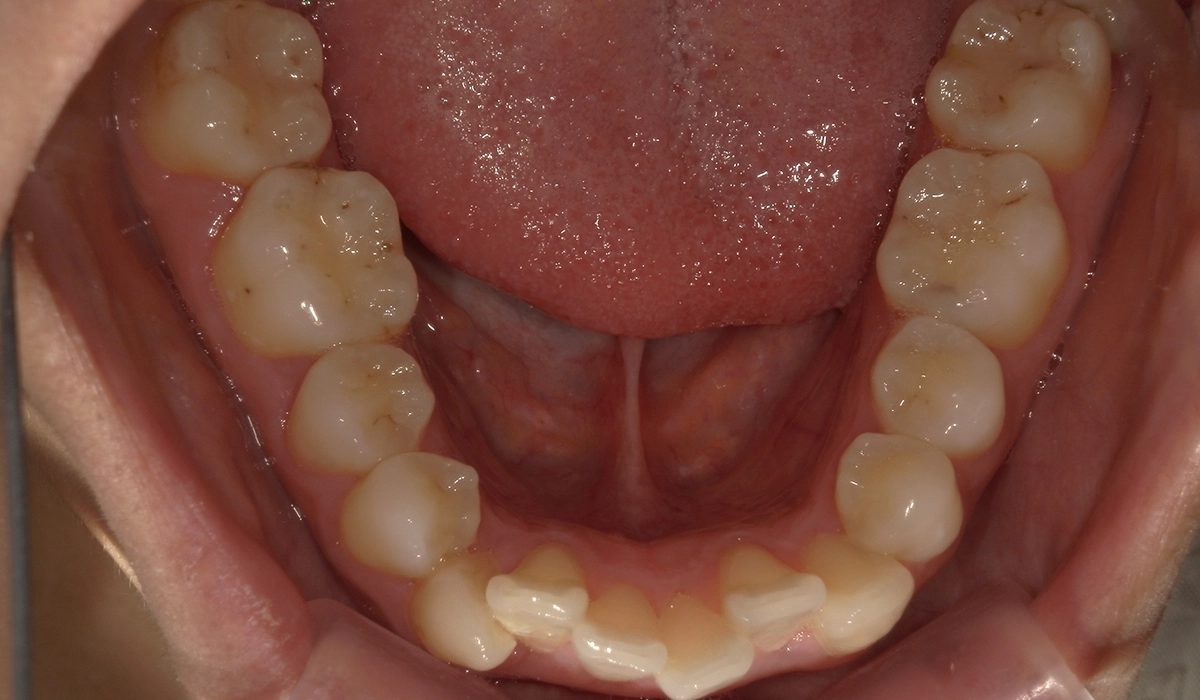

術前:下顎

術後:下顎